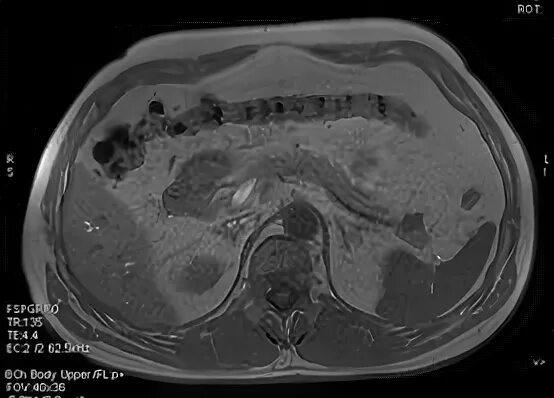

Гиподенсивное образование что это значит